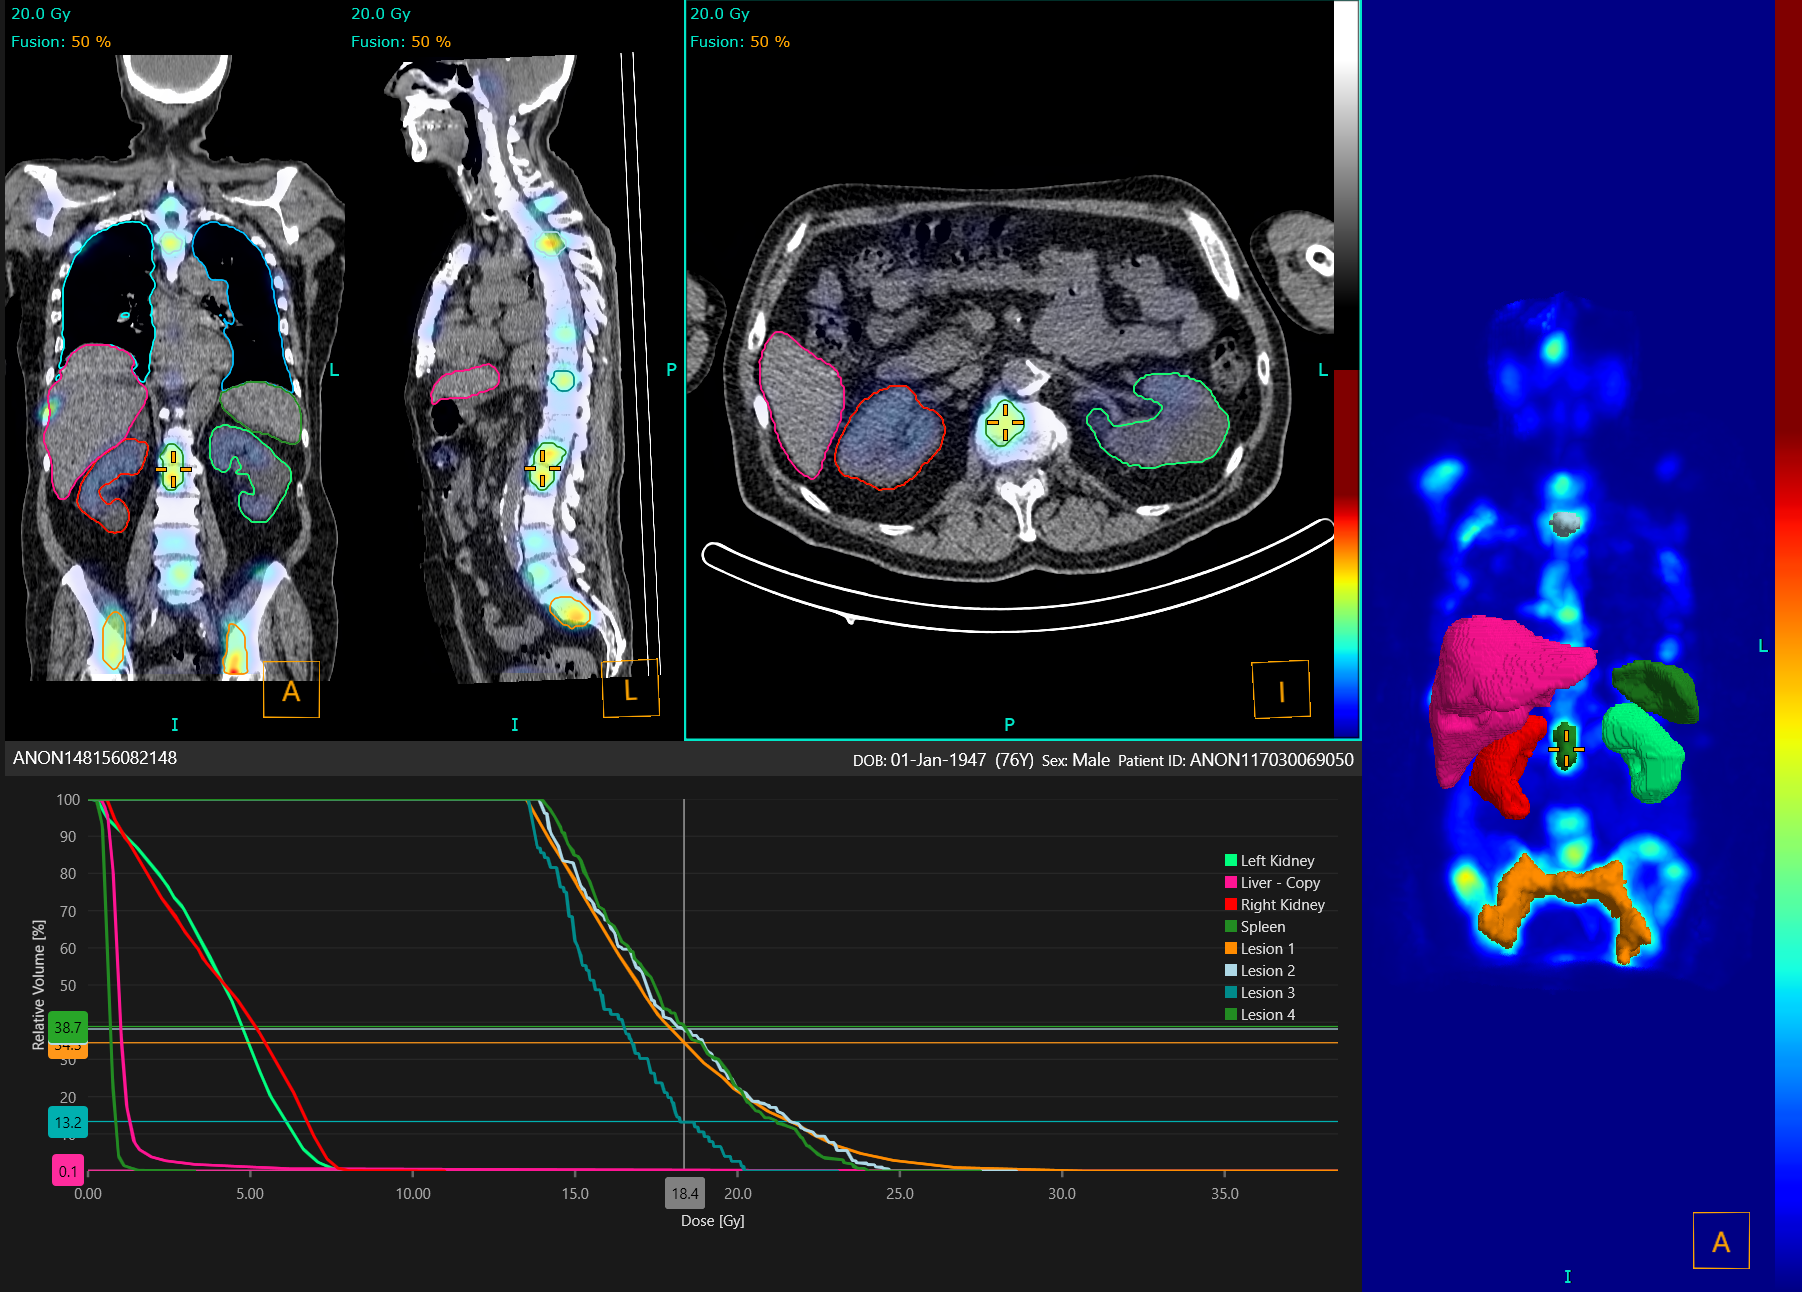

Liver, kidney, spleen, and lung segmentation algorithm runs in the background while you work, saving time during dosimetry analysis and reducing operator variability.

Liver, kidney, spleen, and lung segmentation algorithm runs in the background while you work, saving time during dosimetry analysis and reducing operator variability. All segmentation can be adjusted by the user. Assess region dose coverage using dose-volume histograms and export regions as DICOM SEG, RTSS, or NIfTI file format.

Quantify total metabolic tumor volume even in the most challenging cases with a versatile toolkit including single click lesion segmentation, thresholding, and splitting tools. Use the blob-splitter to help differentiate clinically relevant uptake from physiological or edit with a 3D paintbrush. Measure ‘DMax’* for disseminated disease to quantify spread. Flexible and intuitive, region drawing has never been so easy.